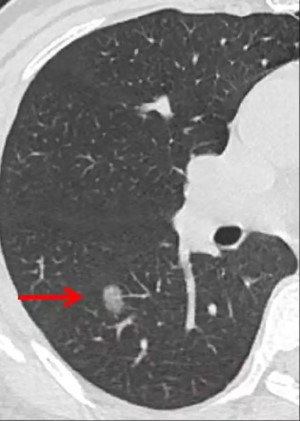

磨玻璃结节是一种在肺部影像学检查中发现的比周围正常肺组织密度稍增高,但是又低于实性结节的密度,其名称来源于这种影像效果与日常见到的半透明磨砂玻璃非常相似,因此得名。

磨玻璃结节有可能是肺癌的早期表现之一,但并不等同于磨玻璃结节就一定是早期的肺癌,磨玻璃结节只是一种影像上的表现,并不是一个病理诊断,以上提到的一些良性病变有时也同样可以表现为磨玻璃结节。因此,医生会根据具体情况可能建议进一步检查以确定其性质。早期肺癌是指肺癌在肺内的生长早期时被发现,CT检查可能表现为肺结节或磨玻璃结节(GGO)改变。